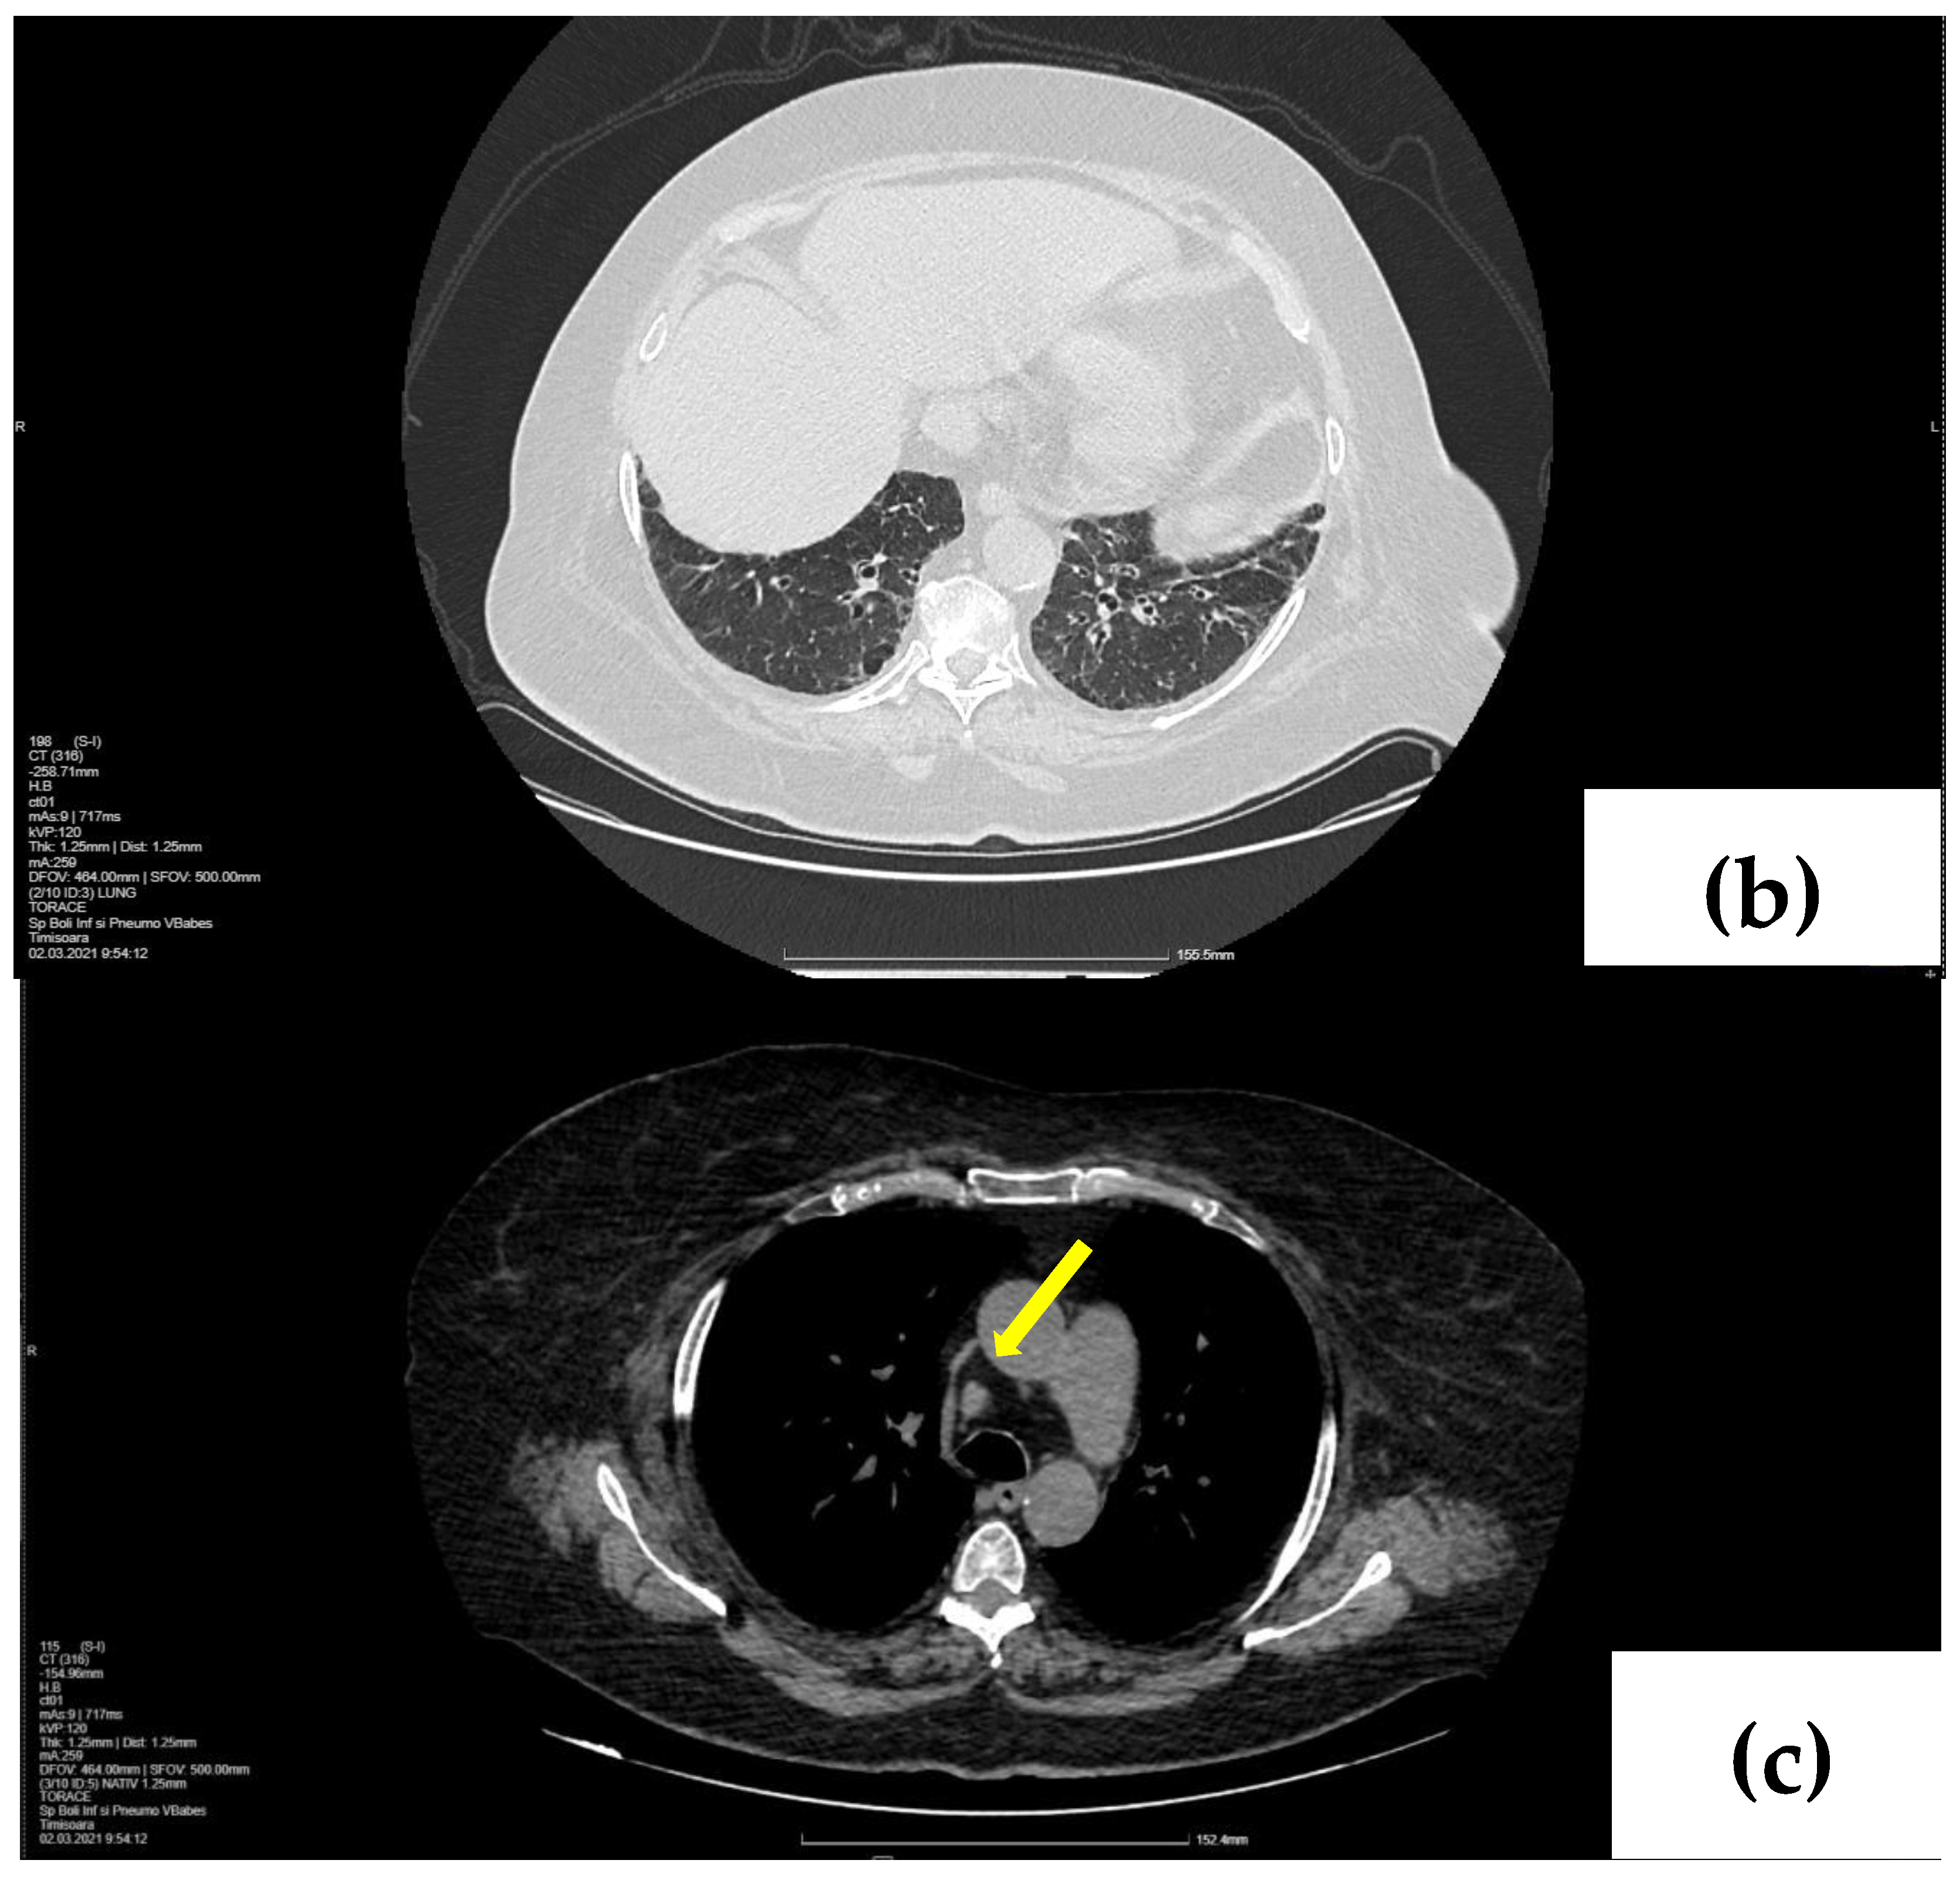

2.1. Laboratory, Radiological, and Histological Examinations